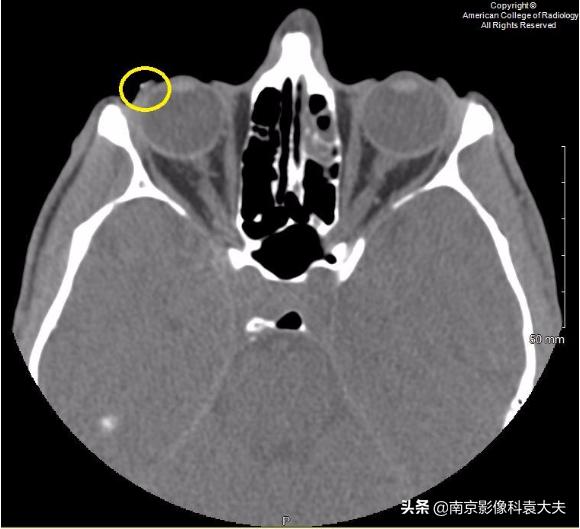

上图 眼球轴位非对比CT图像显示右侧眼睑外侧或巩膜表面可见点状异物(黄圈),发现巩膜上异物,我们应提高对角膜裂伤或其他眼球损伤的怀疑程度。

前部的隐形眼镜可以类似这种表现,临床上必须予以排除。对于角膜异物,应仔细检查相关的眼球穿透伤、球后血肿和面部/眶骨折。